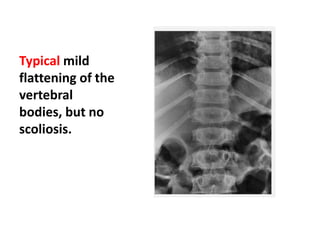

Typical mild

flattening of the

vertebral

bodies, but no

scoliosis.